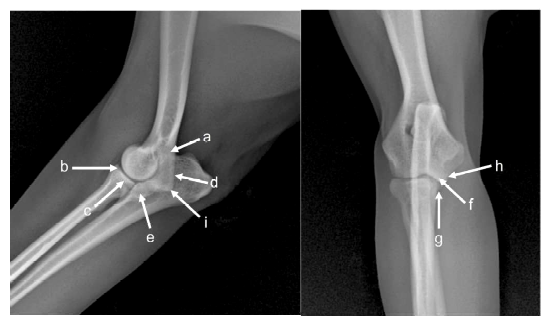

Las imágenes fueron evaluadas por el autor que cuenta con cinco años de experiencia en la interpretación de imágenes diagnósticas, siguiendo las recomendaciones de la IEWG para el diagnóstico de la DC y teniendo en cuenta los sitios de la localización de las lesiones para la graduación de la osteoartrosis (OA) en el codo (Hazewinkel 2018) (Figura 1).

Figura 1. Localización de lesiones de osteoartrosis (OA) de codo. a. Superficie proximal del proceso ancóneo. b. Zona craneal de la cabeza del radio. c. Borde craneal del proceso coronoides medial. d. Superficie caudal de la cresta condilar lateral. e. Esclerosis de la escotadura troclear, en la base del proceso coronoides. f. Sobre la superficie medial del epicóndilo. g. En el borde medial del proceso coronoides medial. h. Hendidura del hueso subcondral: lesión OCD. i. Borde distal de cóndilo humeral (Entesiopatía flexora primaria). (Hazewinkel, 2018). Tomado de: Inovet -Pequeñas especie animales https://inovet.co/